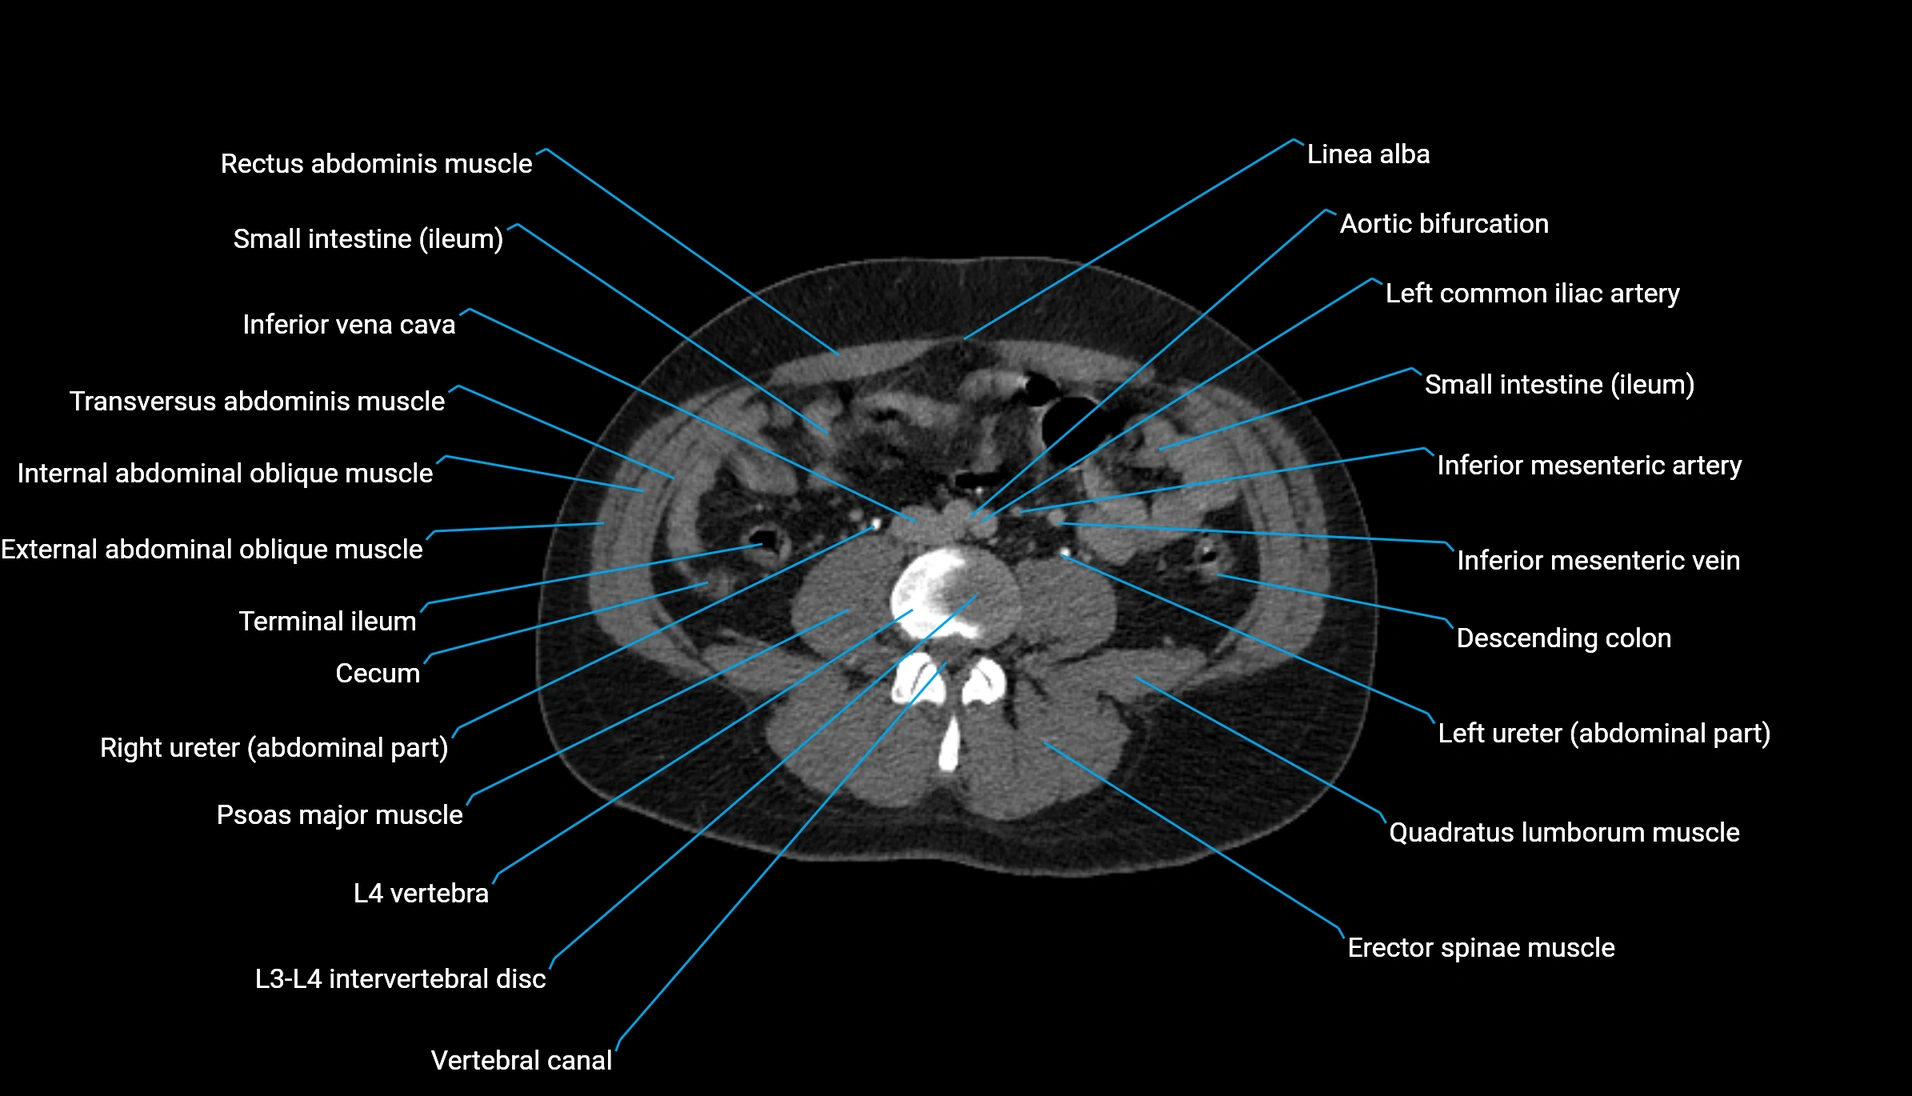

CT Appearance

Non-contrast CT:

-

Demonstrates cortical bone of acetabular rim in excellent detail

Detects fractures, dysplasia, retroversion, or bony overcoverage (pincer impingement)

3D reconstructions used in preoperative hip surgery planning

CT VRT 3D image

CT image